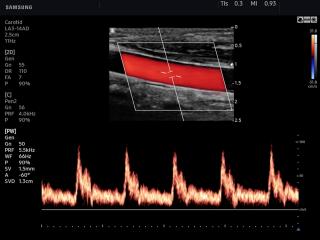

Common carotid artery, CFM & PW

V7. Common carotid artery, CFM & PW.